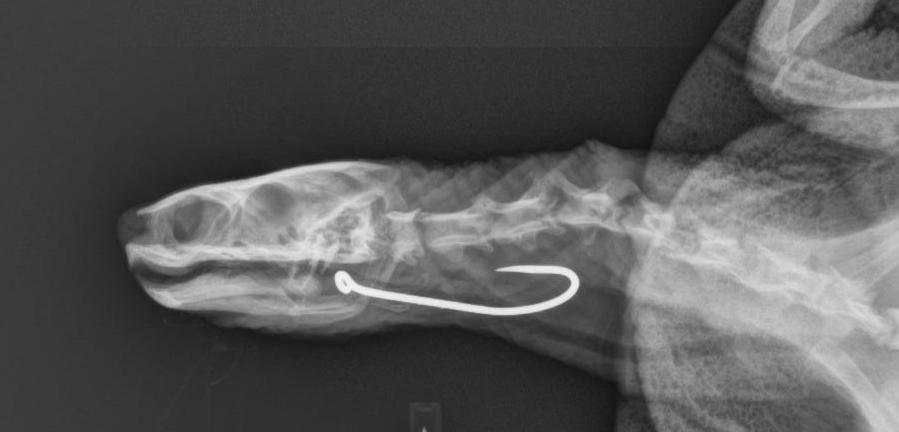

The female Murray River Turtle was rescued from a yard in Nyngan by a concerned member of the public who noticed some fishing line protruding from the animal’s mouth. She was transferred to the Wildlife Hospital in Dubbo where x-rays revealed a large fishing hook was penetrating into her oesophagus and the attached line had cut into the corner of her mouth. Blood tests showed the turtle was dehydrated, suggesting that she had been injured for some time and unable to eat and drink.

The Zoo’s veterinary team got to work quickly, anaesthetising her and surgically removing the hook and delicately repairing the damage to the neck and mouth.